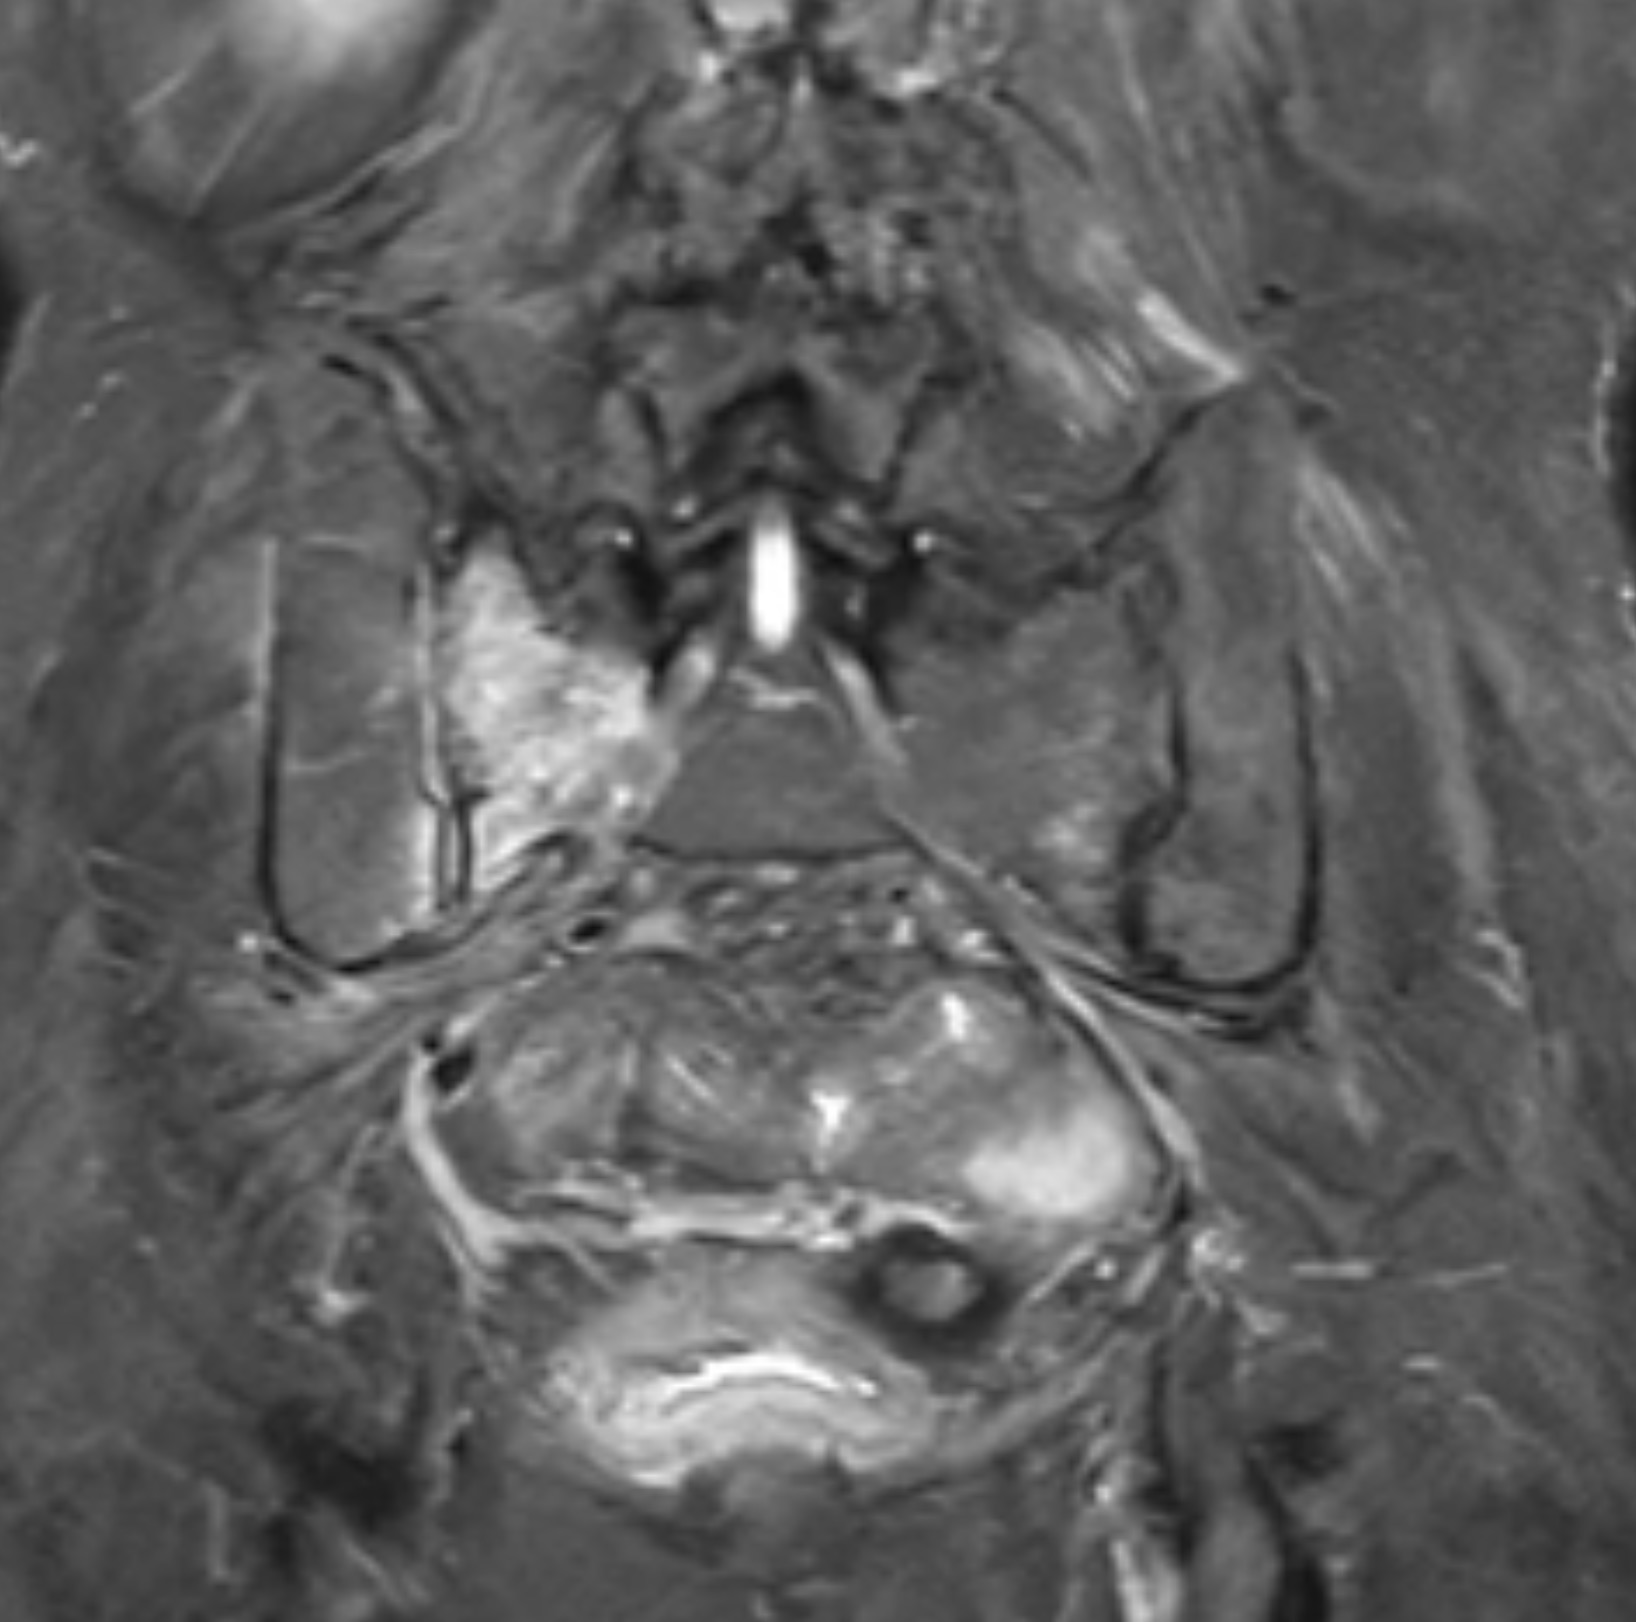

MRI คือมาตรฐานทองคำ เพราะเห็นรอยร้าวและการบวมภายในกระดูก (bone marrow edema) ชัดเจน แม้ X-ray ปกติในระยะแรก

การตรวจเพิ่มเติมอาจรวมถึง:

- X-ray เชิงกราน (เพื่อดูโครงสร้างและความมั่นคง)